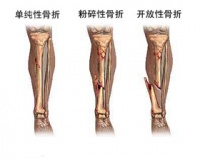

直接暴力多见为压砸、冲撞、打击致伤,骨折线为横断或粉碎型;有时两小腿在同一平面折断,软组织损伤常较严重,易造成开放性骨折。有时皮肤虽未破,但挫伤严重,血循不良而发生继发性坏死,致骨外露,感染而成骨髓炎。间接暴力多见为高处跌下,跑跳的扭伤或滑倒所致的骨折;骨折线常为斜型或螺旋型,胫骨与腓骨多不在同一平面骨折。

间接或直接暴力,均可造成两骨折断端重迭、成角或旋转畸形,直接暴力造成者多为胫腓双骨折,间接暴力可造成单一胫骨或腓骨骨折。前者多为横骨折、短斜骨折或粉碎性骨折,骨折缘多在同一平面上,且开放性较多。后者则易造成螺旋形、斜形或粉碎性骨折,骨折缘常不在同一水平缘上,多为闭合性,多见于运动伤或跌落伤。

X线正位片应包括胫腓骨全长,以免漏诊。X线可见骨折线、碎骨片、断端移位等。